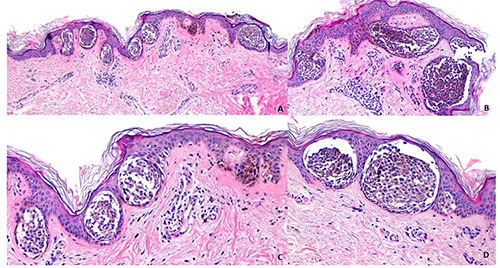

全世界的皮肤癌发病率正在上升。皮肤科医生和组织病理学家之间的清晰沟通以及共享临床图像的可能性至关重要。这项调查旨在描述在意大利临床实践中皮肤科医生和组织病理学家之间的沟通水平。我们招募了一组参加每月在线会议的组织病理学家参与我们的调查。我们收集了关于皮肤科医生提供或不提供黑素细胞/角化细胞病变的临床和皮肤镜图像的习惯的信息。共有63名组织病理学家同意参与。在黑色素细胞病变手术切除后,只有不到15%的组织病理学家收到皮肤科医生的常规临床或皮肤镜图像,而非黑色素瘤皮肤癌的临床和皮肤镜图像只有不到10%的病例收到。我们的调查显示,在意大利,皮肤科医生和病理学家之间的沟通远未达到最佳状态。

Skin cancer incidence is increasing worldwide. Clear communication between dermatologists and histopathologists, along with the possibility of sharing clinical images, is critically important. This survey aims to depict the level of communication between dermatologists and histopathologists in clinical practice in Italy. A group of histopathologists participating in monthly online meetings was recruited to participate in our survey. We collected information regarding dermatologists' habits in providing or not providing clinical and dermatoscopic images of melanocytic/keratinocytic lesions. A total of 63 histopathologists agreed to participate. Fewer than 15% of histopathologists receive routine clinical or dermatoscopic images from dermatologists after the surgical excision of a melanocytic lesion, while clinical and dermoscopic images of non-melanoma skin cancers (NMSC) are sent in fewer than 10% of cases. Our survey revealed that, in Italy, the communication between dermatologists and pathologists is far from being optimal.